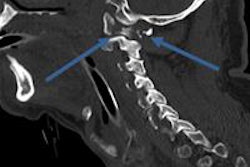

Regional trauma networks have been established in Germany to improve care of severely injured persons, and to ensure appropriate patient treatment in a short time; the transfer of radiological image data between the connected hospitals over the Internet is an important issue, explained the authors in an article published in the November edition of the Journal of Medical Systems (November 2014, Vol. 38:11, pp. 137).

They sought to characterize radiological image transfer patterns within the TraumaNetwork NorthWest (founded in 2009) and analyze various compression options. Their goals were to establish an electronic transfer of radiological images (DICOM) between hospitals with heterogeneous software and hardware equipment, to examine the speed and volume of typical transfers, to analyze how the transfer volume could be decreased by different compression algorithms, and to evaluate the overall transfer flow between the hospitals, especially to analyze transfer frequencies and communications structures.

"MedSix" can transfer DICOM-data quickly and easily between hospitals and can be directly connected to the local PACS. Audit data of the routine system were analyzed during 2012 to identify typical characteristics of radiological image exchanges. Five different compression methods were compared by a simulation.

The team analyzed the size of the images between 1 August 2012 and 31 December 2012, and found out that 72% of the images had a size between 500 kB and 550 kB. This is typical for CT images, they added. On average, files were 632 kB, with a median of 518.8 kB. Nearly 60% of the transfers were below 100 MB and 81.6% were below 200 MB. Only 5% needed more than 500 MB space, and the biggest transfer had a size of 524 MB.